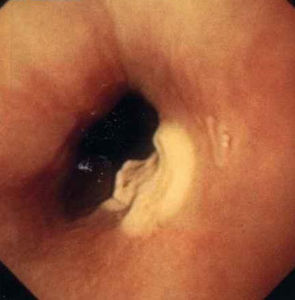

2.纖維食管鏡檢查

大部分平滑肌瘤可經過食管鋇餐診斷,加上纖維食管鏡(實際上常用纖維胃鏡)檢查,檢查準確率可達90%以上,可了解腫瘤的部位、大小、數目及形狀等。鏡檢能見到突出在食管腔中的腫物,表面黏膜完整光滑平展,皺襞消失,呈淡紅色半透明,肌瘤邊緣隱約可見,吞咽活動時,可見腫物上下輕度活動,管腔狹窄的不多。